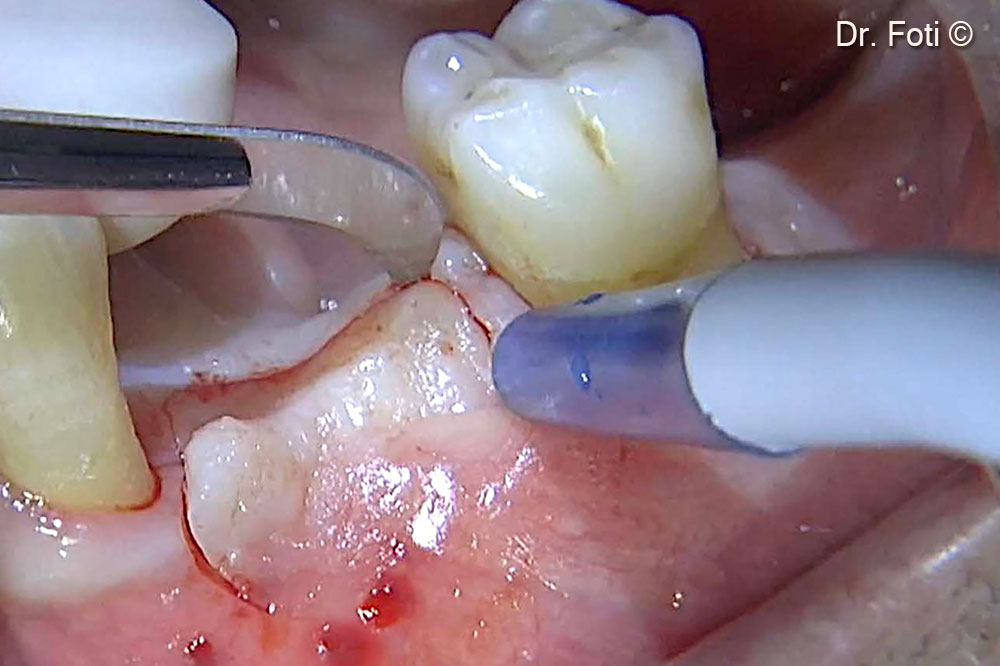

Two implants are placed. The cortical bone is drilled to promote bleeding and recruit Mesenchymal Stem Cells